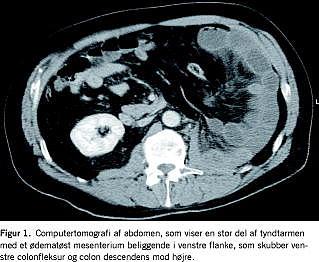

Ved den aktuelle indlæggelse fandtes patienten tydeligt smertepåvirket og klamtsvedende, blodtryk 187/106 mmHg, puls 60, temperatur 35,7 °C. Abdomen var direkte øm svarende til venstre nyreloge. Akut computertomografi af abdomen med intravenøs og peroral kontrast viste sequelae efter venstresidig nefrektomi i form af koagler eller hæmatom og fri væske intraabdominalt samt tegn på intern herniering af en stor del af tyndtarmen med ødematøst mesenterium til venstre flanke. Tyndtarmskonglomeratet skubbede venstre colonfleksur og colon descendens mod højre (Figur 1 ). Patienten blev akut laparotomeret, der fandtes blodtingeret væske intraabdominalt og 125 cm dilateret, men vitalt tyndtarmskonglomerat som havde hernieret sig igennem en 5 cm stor defekt i mesenteriet af venstre colonfleksur. Tyndtarmskonglomeratet blev reponeret, resektion fandtes ikke indiceret, og defekten blev lukket uden brug af mesh. Det postoperative forløb var ukompliceret, og patienten kunne udskrives efter syv dage.